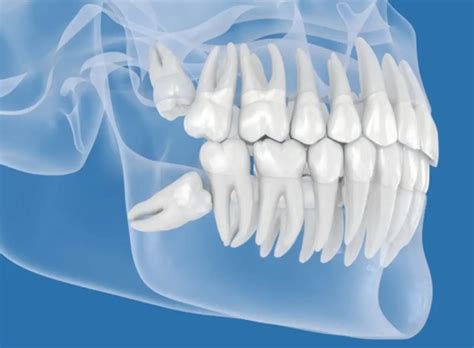

Posiciones de las muelas del juicio.

Las muelas del juicio pueden desarrollarse en ángulo hacia el segundo molar, contra la parte posterior de la boca. También pueden crecer de forma horizontal, empujando al diente más cercano, es decir, aparenta estar acostada en el maxilar, o de manera recta hacia arriba o hacia abajo. O puede quedar retenida de forma parcial o total dentro de la encía. No atender a tiempo la salida de estos dientes puede traer como consecuencia serias complicaciones y enfermedades bucales graves:

Posiciones de las muelas del juicio. Cuando aparecen las muelas del juicio, pueden darse tres situaciones diferentes:

- Que tengan espacio suficiente para erupcionar (salir) y colocarse en su posición correcta - si es así, las muelas del juicio serán una muela más y no habrá que hacer nada diferente al cuidado dental habitual.

- Que erupcionen parcialmente- esta situación puede generar infecciones recurrentes, por la dificultad de limpiar adecuadamente la zona. De las tres posibilidades, es la que más molestias genera y el tratamiento suele ser la extracción.

- Que no tengan espacio para salir, quedando atrapadas dentro del hueso maxilar - en este caso, se habla de «muelas incluidas», a las que hay que ir estudiando su posición y sus posibles complicaciones a lo largo del tiempo.

En los dos últimos casos, las muelas pueden comenzar a “empujar” en cualquier momento para intentar erupcionar, lo que puede producir dolores en la zona.